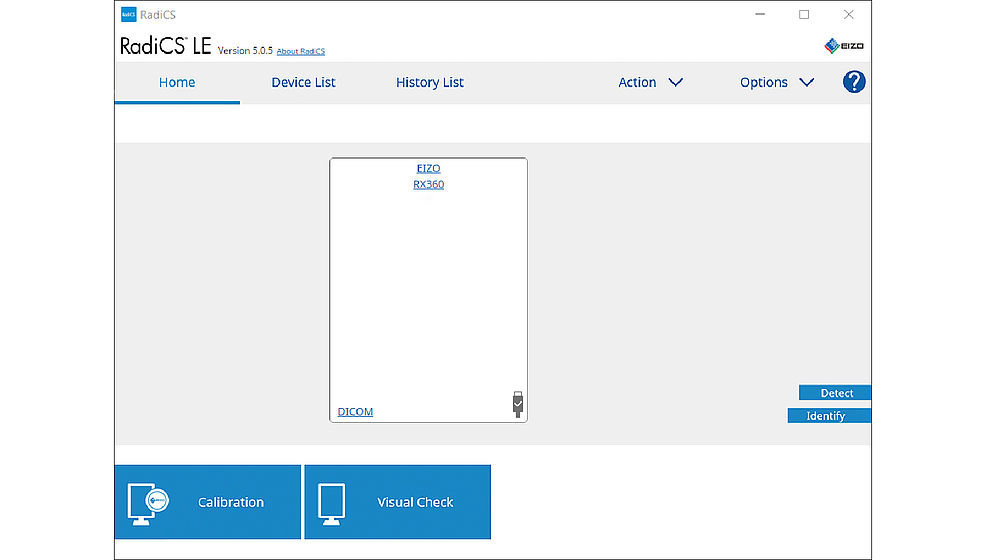

Program RadiCS LE służy do kalibrowania monitorów RadiForce i zarządzania uzyskanymi w ten sposób danymi. Pozwala łatwo sprawdzić informacje takie jak czas pracy monitora czy numery inwentaryzacyjne.

Oprócz tego RadiCS LE ma zintegrowany wygaszacz podświetlenia, pomagający obniżyć pobór mocy i skrócić czas pracy monitora, gdy ten nie jest używany. Funkcja Mouse Warp dba natomiast o to, by kursor myszy nie utykał między krawędziami ekranów w konfiguracjach z monitorami o różnej rozdzielczości.